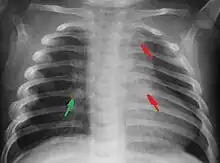

Most nations with child abuse laws deem the deliberate infliction of serious injuries, or actions that place the child at obvious risk of serious injury or death, to be illegal.[38] Bruises, scratches, burns, broken bones, lacerations—as well as repeated "mishaps", and rough treatment that could cause physical injuries—can be physical abuse.[39] Multiple injuries or fractures at different stages of healing can raise suspicion of abuse.

C. Henry Kempe and his colleagues were the first to describe the battered-child syndrome in 1962.[42] The battered-child syndrome is a term used to describe a collection of injuries that young children sustain as a result of repeated physical abuse or neglect.[43][44] These symptoms may include: fractures of bones, multiple soft tissue injuries, subdural hematoma (bleeding in the brain), malnutrition, and poor skin hygiene.[44][45]

The immediate physical effects of abuse or neglect can be relatively minor (bruises or cuts) or severe (broken bones, hemorrhage, death). Certain injuries, such as rib fractures or femoral fractures in infants that are not yet walking, may increase suspicion of child physical abuse, although such injuries are only seen in a fraction of children suffering physical abuse.[94][95] Cigarette burns or scald injuries may also prompt evaluation for child physical abuse.[96]